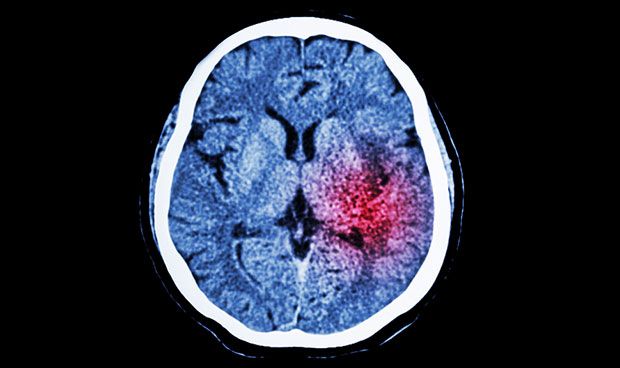

Un nuevo fármaco para el tratamiento eficaz de la hemorragia intracerebral

El ictus multiplica los riesgos de una insuficiencia cardiaca